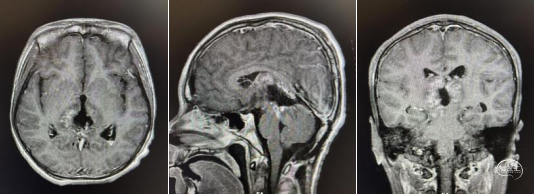

头部MRI显示:松果体区可见一形态不规则肿块,大小约52mm*50mm*51mm,其内信号混杂,呈短-长T1,短-稍长-长T2信号,增强后实质部分可见明显不均匀强化。肿瘤部分突入三脑室内,与三脑室左侧壁及左侧丘脑分界不清,中脑导水管受压变窄,三脑室及侧脑室扩张。右侧脑室前角可见一引流管影。

术前MRI